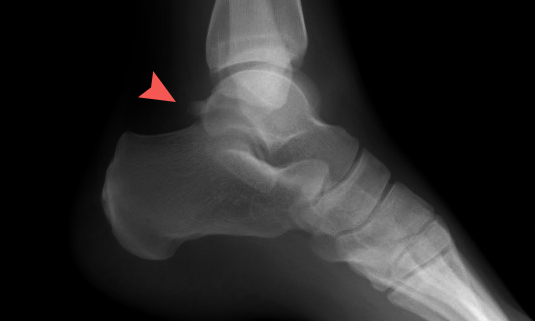

| [건강설계]아킬레스건염일까? 후방충돌증후군일까? | |||||

[건강설계]아킬레스건염일까? 후방충돌증후군일까? |